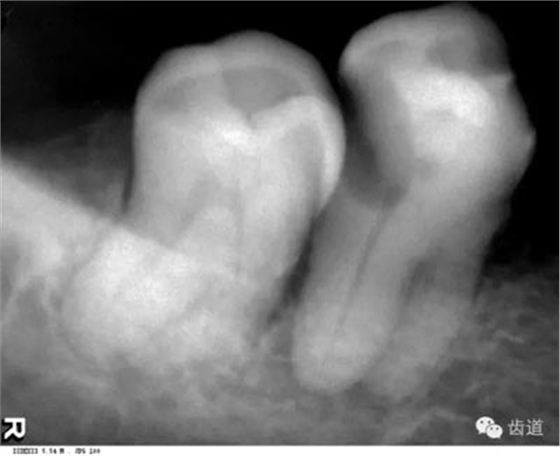

是上下頜骨包圍牙根的突起部分,又稱牙槽突或牙槽嵴。X線片上牙槽骨所顯示的密度較牙低。上牙槽骨的密質(zhì)骨薄,松質(zhì)骨多,即骨小梁數(shù)目多,相交處呈密度高的點(diǎn)狀影像,骨髓腔則呈點(diǎn)狀密度低的影像,固上牙牙槽骨的骨小梁結(jié)構(gòu)X線片上呈顆粒狀影像;

牙槽骨:下牙槽骨密質(zhì)骨厚而松質(zhì)骨少,骨小梁多呈水平方向排列,骨髓腔呈三角形和大小不等的圓形密度低的影像,所以下牙槽骨的骨小梁結(jié)構(gòu)呈網(wǎng)狀結(jié)構(gòu)